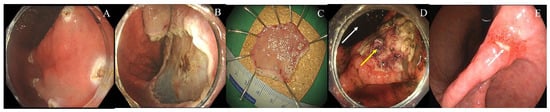

Ilaprazole Versus Esomeprazole for Artificial Ulcer Healing After Gastric Endoscopic Submucosal Dissection: A Single-Center Retrospective Study

by Dae-Gon Ryu, Su-Jin Kim, Su-Bum Park, Jin-Ook Jang, Woo-Jin Kim, Cheol-Min Lee, Jin-Hyuck Cho, Eun-Jung Choi and Cheol-Woong Choi

J. Clin. Med. 2026, 15(9), 3357; https://doi.org/10.3390/jcm15093357 - 28 Apr 2026

Background: Endoscopic submucosal dissection (ESD) is widely used for the treatment of gastric neoplasia; however, the large artificial ulcer created during the procedure requires several weeks to heal. Although proton pump inhibitors (PPIs) are routinely administered after ESD, evidence comparing individual PPIs [...] Read more.

Background: Endoscopic submucosal dissection (ESD) is widely used for the treatment of gastric neoplasia; however, the large artificial ulcer created during the procedure requires several weeks to heal. Although proton pump inhibitors (PPIs) are routinely administered after ESD, evidence comparing individual PPIs for artificial ulcer healing in real-world practice remains limited. This study compared the effectiveness of oral ilaprazole and oral esomeprazole as maintenance therapy after gastric ESD. Methods: This retrospective single-center study included patients who underwent gastric ESD between January 2020 and December 2024. All patients received intravenous PPI therapy for two days after ESD and were subsequently prescribed either oral ilaprazole 20 mg once daily or esomeprazole 40 mg once daily for 8 weeks. The primary outcome was complete artificial ulcer healing at 8 weeks. The secondary outcome was post-discharge delayed bleeding. Results: A total of 229 patients were analyzed (147 in the esomeprazole group and 82 in the ilaprazole group). The overall 8-week ulcer healing rate was 94.3%, with no significant difference between the ilaprazole and esomeprazole groups (97.5% vs. 92.5%, p = 0.114). In multivariate analysis, artificial ulcer size ≥ 30 mm was the only independent predictor of incomplete ulcer healing (odds ratio 20.850, 95% confidence interval 1.884–230.712, p = 0.013). Post-discharge delayed bleeding occurred in 8 patients (3.4%), all in the esomeprazole group (p = 0.032). No treatment-related adverse events were observed. Conclusions: Ilaprazole demonstrated ulcer-healing efficacy comparable to esomeprazole after gastric ESD. Artificial ulcer size ≥ 30 mm was the principal determinant of delayed healing, whereas the treatment group was not independently associated with healing outcomes. Ilaprazole may be considered a reasonable maintenance PPI option in routine post-ESD management. Full article

Show Figures

Figure 1